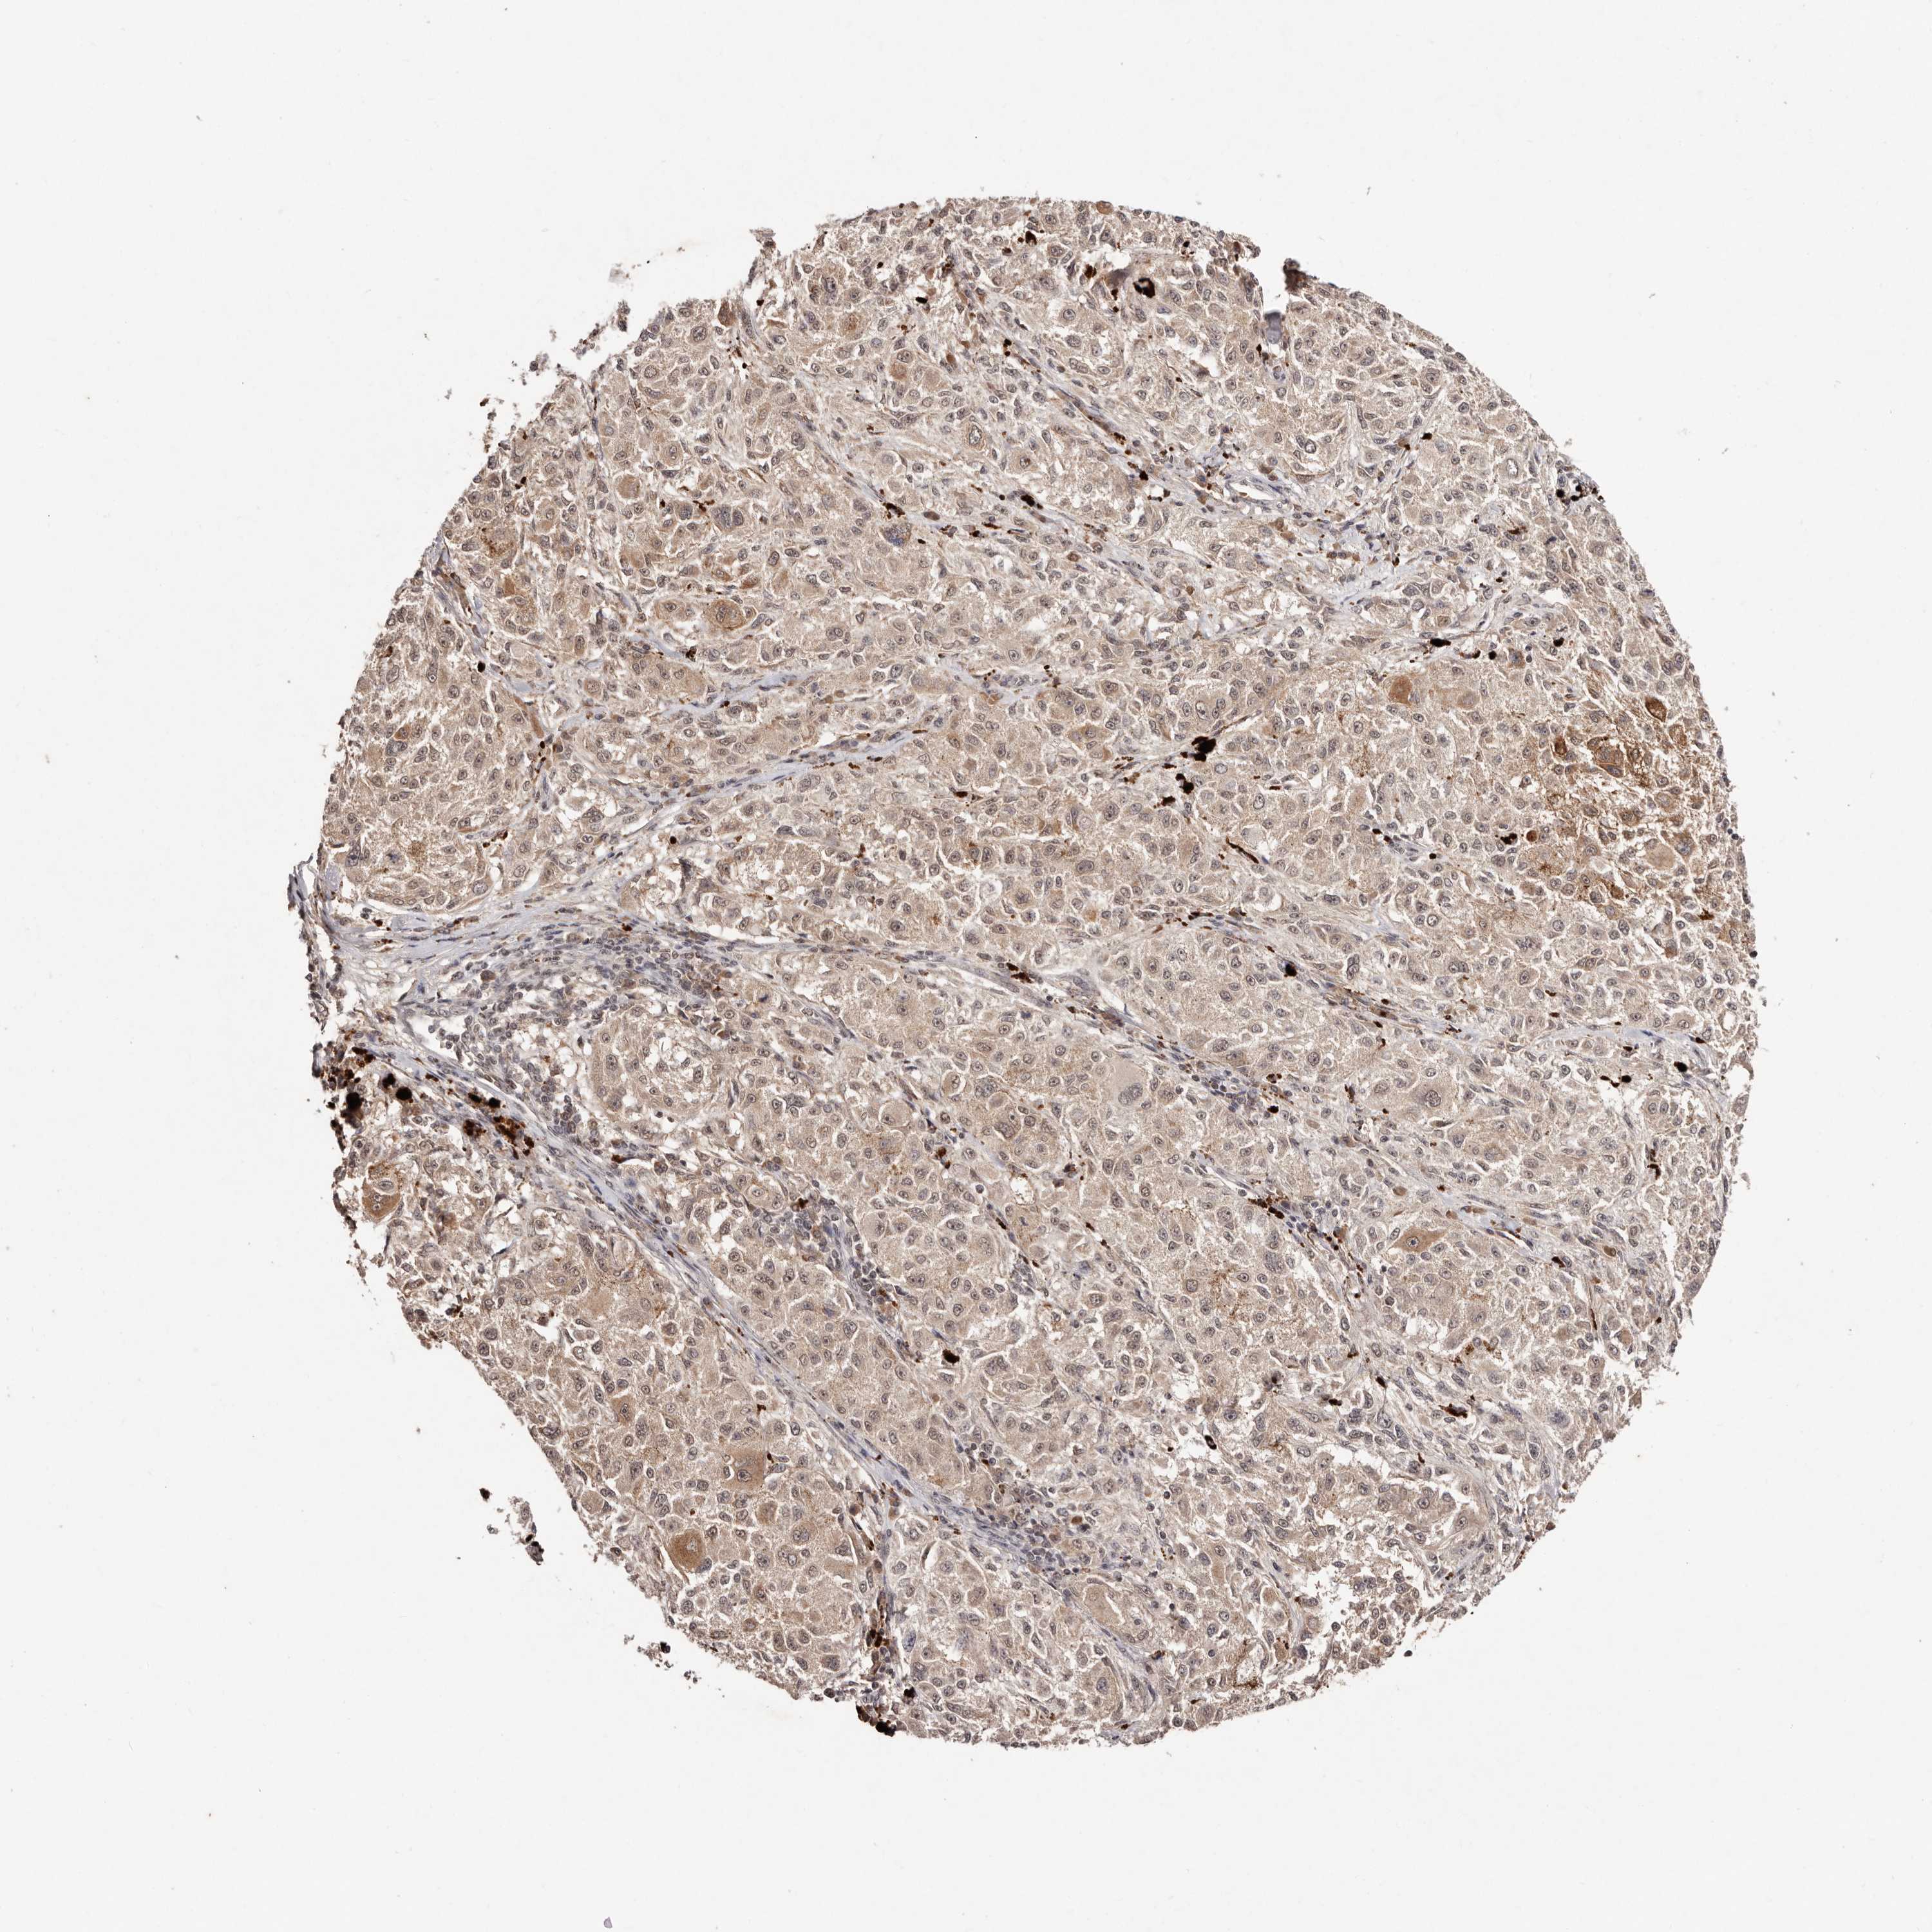

MELANOMA - Protein expressioni

A mouse-over function shows sample information and annotation data. Click on an image to view it in a full screen mode. Samples can be filtered based on level of antibody staining by selecting one or several of the following categories: high, medium, low and not detected. The assay and annotation is described here.

Note that samples used for immunohistochemistry by the Human Protein Atlas do not correspond to samples in the TCGA dataset.

Antibody stainingi

Antibody staining in the annotated cell types in the current human tissue is reported as not detected, low, medium, or high, based on conventional immunohistochemistry profiling in selected tissues. This score is based on the combination of the staining intensity and fraction of stained cells.

Each image is clickable and will lead to virtual microscopy that enables deeper exploration of all samples and also displays staining intensity scores, fraction scores and subcellular localization as well as patient and tissue information for each sample.

Antibody HPA029390

Antibody HPA029391

Staining

High

Medium

Low

Not detected

Intensity

Strong

Moderate

Weak

Negative

Quantity

>75%

75%-25%

<25%

None

Location

Nuclear

Cytoplasmic/membranous

Cytoplasmic/membranous,nuclear

Malignant melanoma, NOS

Malignant melanoma, Metastatic site